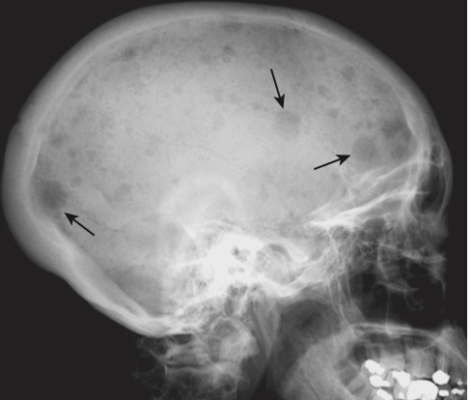

- Các tổn thương huỷ xương có biên rõ trong các xương dài, được gọi là các khối u Brown và hình ảnh dạng muối tiêu (salt-and-pepper) của xương sọ (Hình -4).